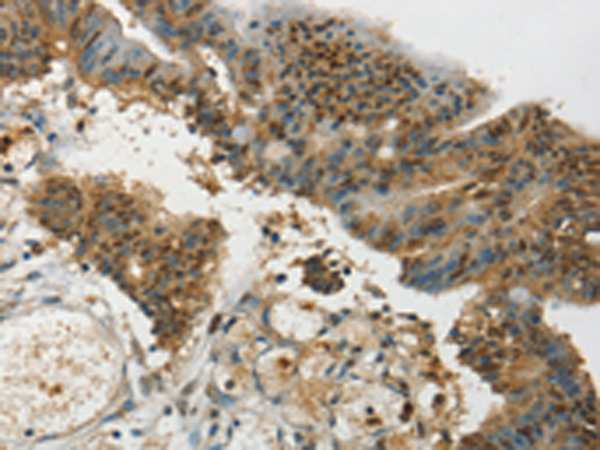

分类: 科研抗体货号: P05284别名: SAF2; SIGLEC-8; SIGLEC8L应用: WB,IHC反应种属: Human